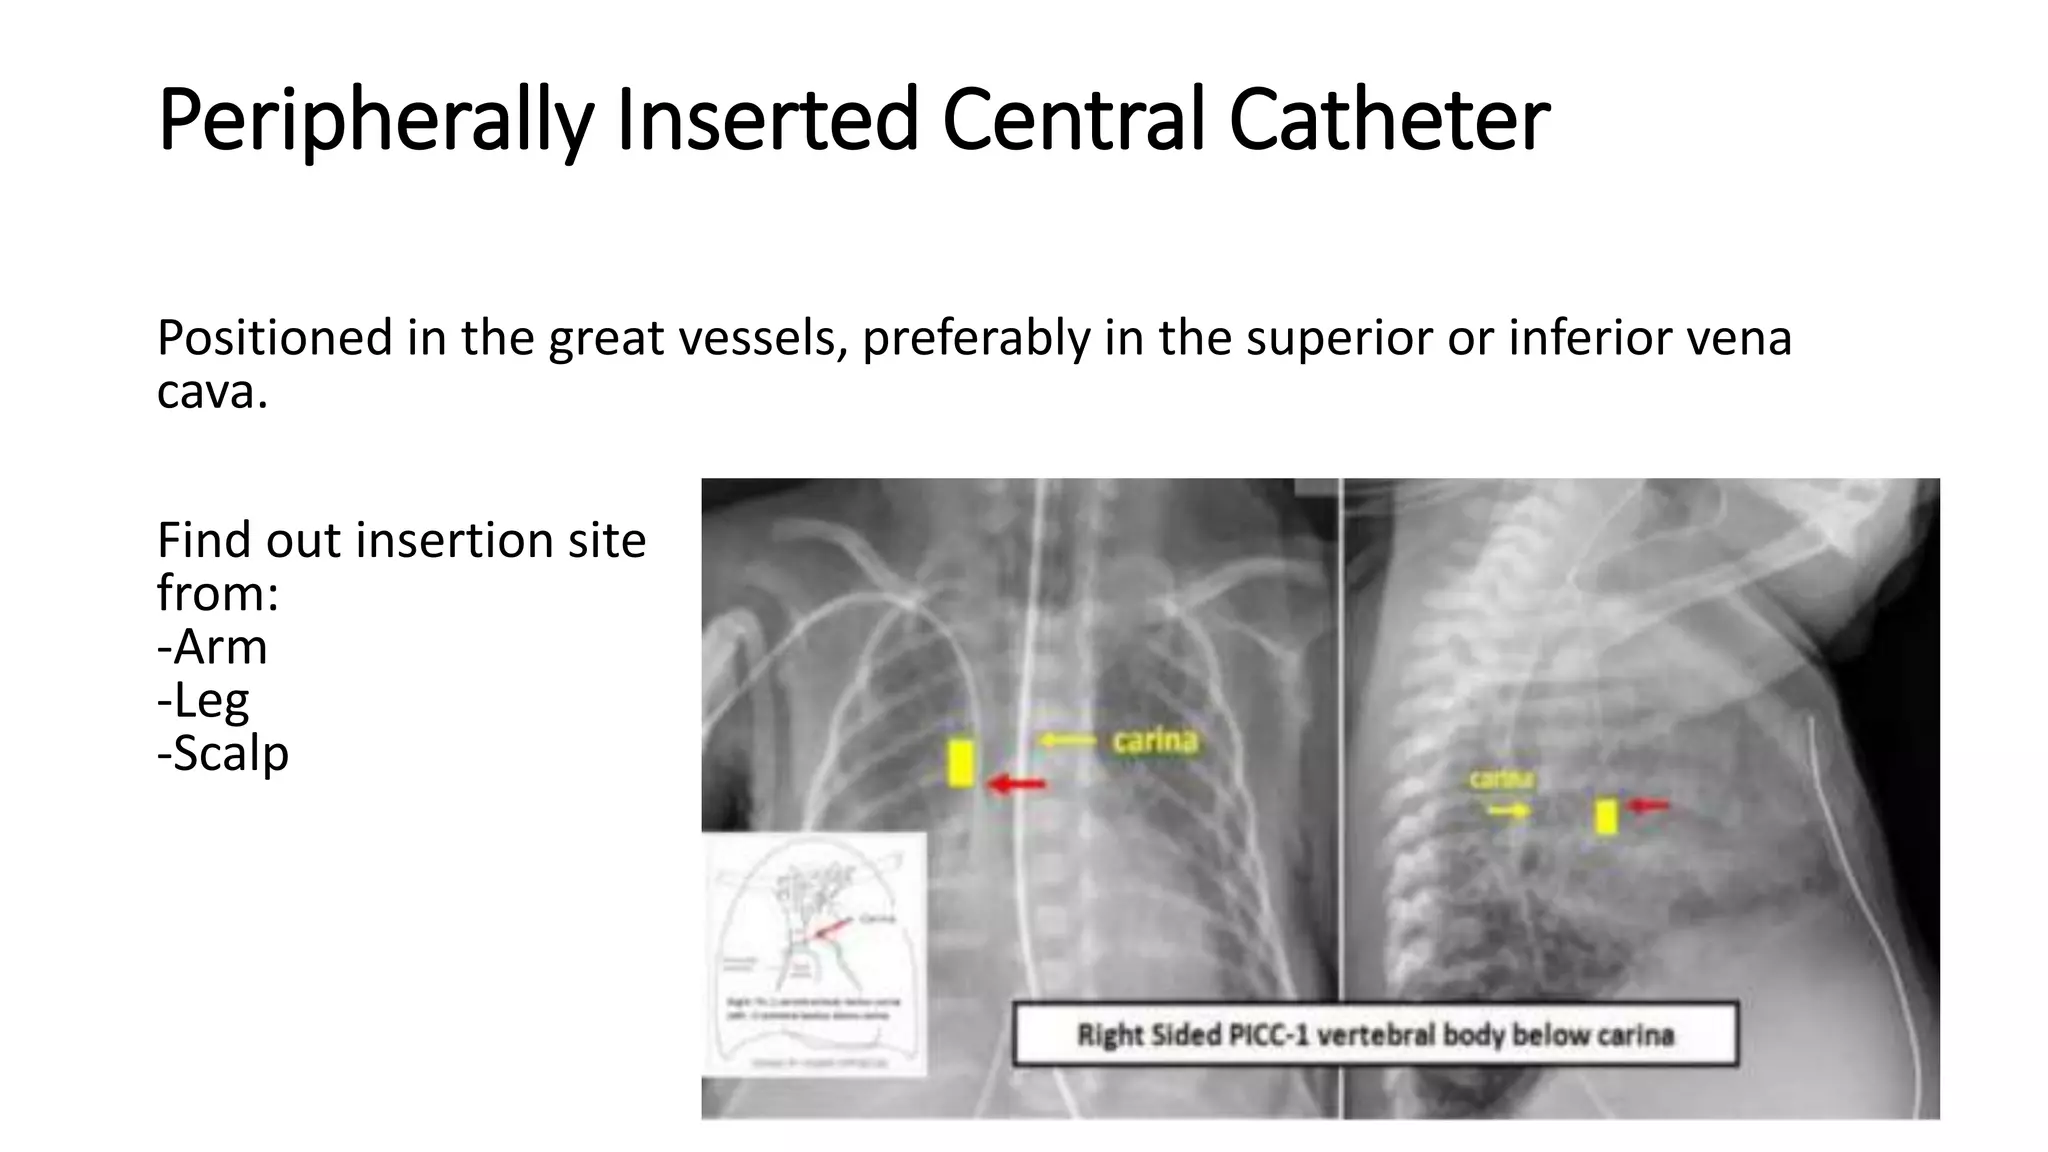

This document provides an overview of neonatal chest x-rays, including when they should and should not be performed, what a normal x-ray looks like, common positions of tubes and catheters, and common causes of respiratory distress in neonates. It discusses the appearance of a normal chest x-ray as well as conditions like respiratory distress syndrome, transient tachypnea of the newborn, meconium aspiration syndrome, and pneumonia. Surgical conditions like diaphragmatic hernia and esophageal atresia are also reviewed.